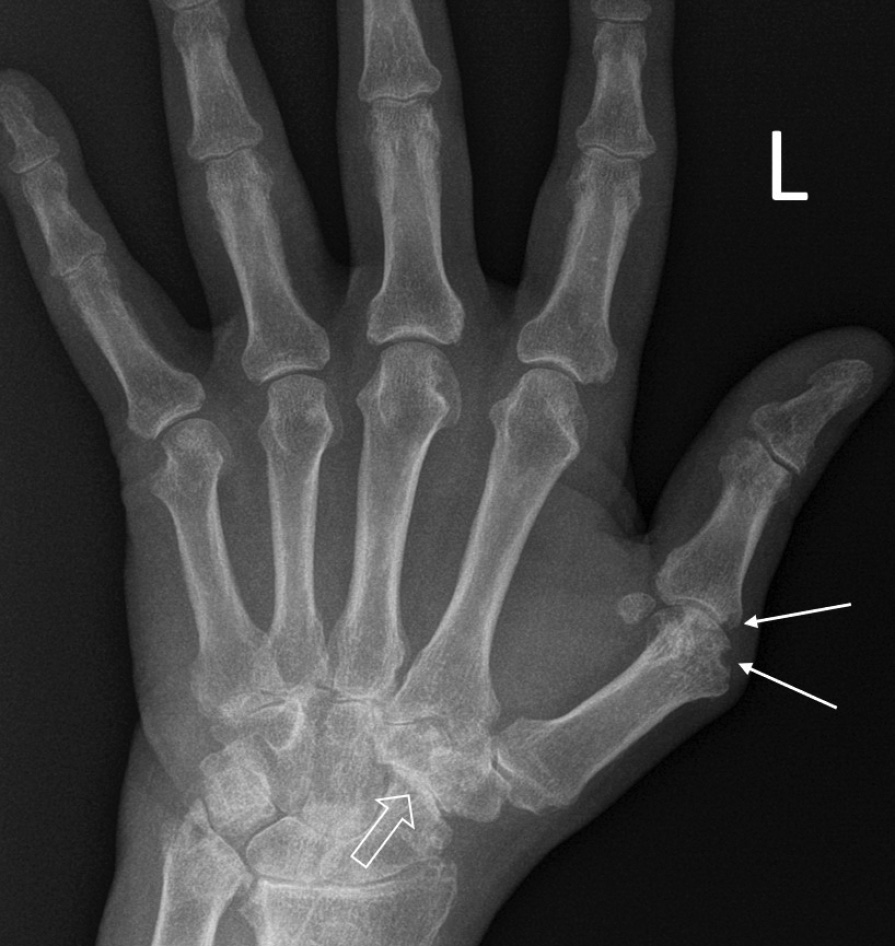

При компьютерной томографии органов грудной клетки данных за «свежие» очаговые и инфильтративные изменения не получено. Увеличения лимфатических узлов подмышечных областей, средостения, корней легких не выявлено. Отмечался усиленный грудной кифоз, обызвествление передней продольной связки, на всем уровне исследования определялись передне-боковые спондилофиты, а также анкилоз большинства реберно-поперечных суставов. По данным рентгенографии кистей (рис. 1, 2) и стоп (рис. 3, 4) диагностированы признаки эрозивного артрита, анкилоз суставов запястья. По данным МРТ крестцово-подвздошных суставов (КПС) определялся неравномерный анкилоз КПС, хрящи по суставным поверхностям неравномерной толщины, примерно на половине протяжении сустава отсутствуют, «суставной промежуток» облитерирован. Неравномерность и нечеткость контура суставных поверхностей за счет множества краевых эрозий справа, единичных – слева, с наличием остеокластоза, в нижнем отделе слева по смежным отделам определяются участки трабекулярного отека, данная находка клинически интерпретирована как двусторонний активный сакроилиит (рис. 5, 6).

Рис. 1. Рентгенограмма левой кисти в прямой проекции. Краевые эрозии суставных поверхностей первого пястно-фалангового сустава (тонкие стрелки), сужение суставных щелей суставов запястья с формированием анкилозов (толстая стрелка)

Рис. 2. Рентгенограмма правой кисти в прямой проекции. Краевая эрозия суставной поверхности лучевой кости (тонкая стрелка), множественные анкилозы суставов запястья (толстые стрелки)

В возрасте 40 лет присоединились жалобы на симметричные воспалительные боли в лучезапястных суставах и мелких суставах кистей, резкое снижение объема движения в лучезапястных суставах. При осмотре пациента выявлено: число болезненных суставов – 7, число припухших суставов – 4, положительный симптом поперечного сжатия кистей и стоп, ульнарная девиация мелких суставов стоп. Резко сниженный объем движения в лучезапястных суставах обеих кистей. По данным рентгенологического обследования зафиксированы типичные изменения для РА: резкое неравномерное выраженное сужение суставных щелей, субхондральный склероз в лучезапястных суставах, анкилоз в суставах запястья, пястно-запястных, пястно-фаланговых и межфаланговых суставах. Краевые эрозии оснований основных фаланг двух пальцев; участки кистовидной перестройки костной ткани. Локальное утолщение мягких тканей. При лабораторном обследовании пациента отмечен положительный ревматоидный фактор, высокий титр антицитруллинированных антител, повышение острофазовых белков.